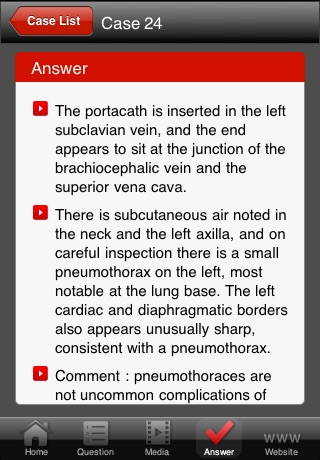

Data interpretation is essential to all clinicians who care for critically ill patients. The ability to recognize common patterns of disease or investigation results is fundamental to establishing the correct diagnosis. This app will be valuable to all critical care clinicians by providing them with instant "experience", so that when they come across something in practice, they will be able to recognize it.